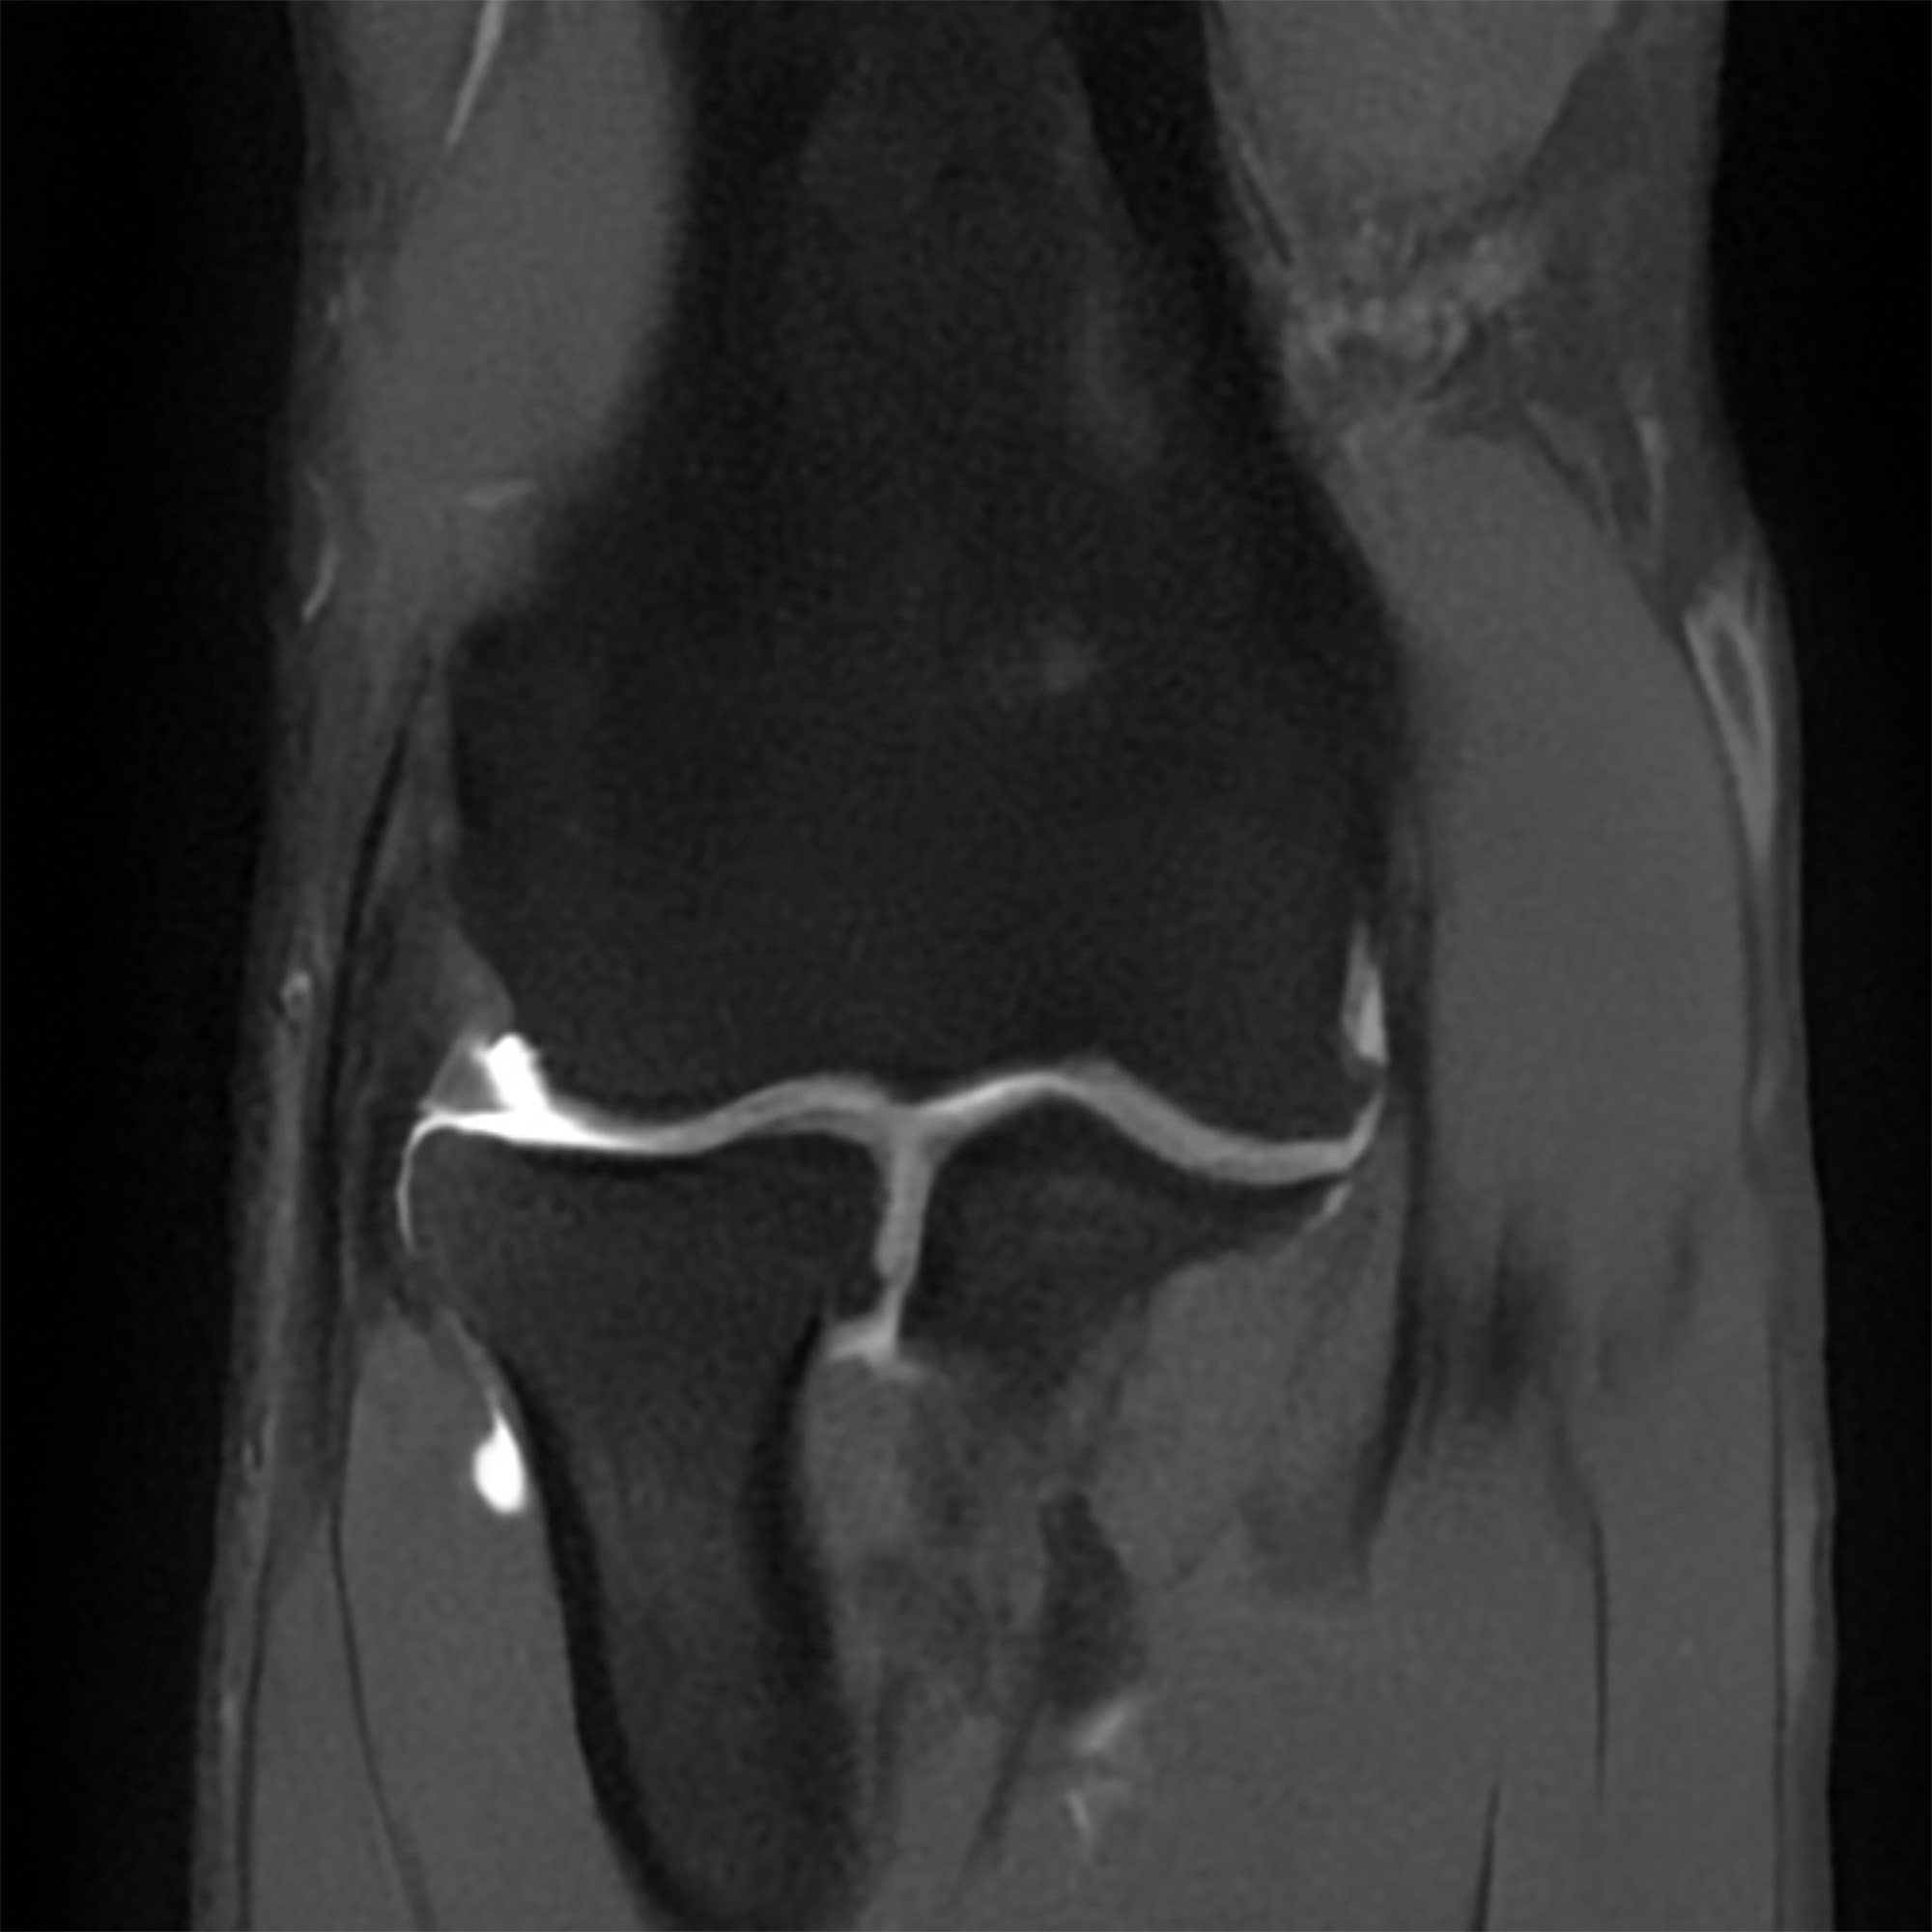

Arthro-IRM images d'examen